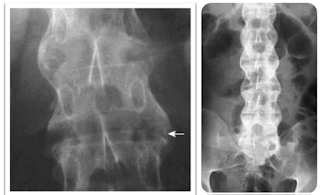

Triệu chứng X-Quang

Viêm khớp cùng chậu hai bên: là dấu hiệu đặc hiệu và xuất hiện

sớm

- GĐ1: Khớp hẹp, diện hơi mờ.

- GĐ2: Khớp hẹp, bờ nham nhở.

- GĐ3: Khớp hẹp nhiều, có chỗ dính.

- GĐ4: Khớp dính hoàn toàn, không còn ranh giới

Chẩn đoán có giá trị ở gđ 2 ở 2 bên hoặc gđ 3-4 ở một bên